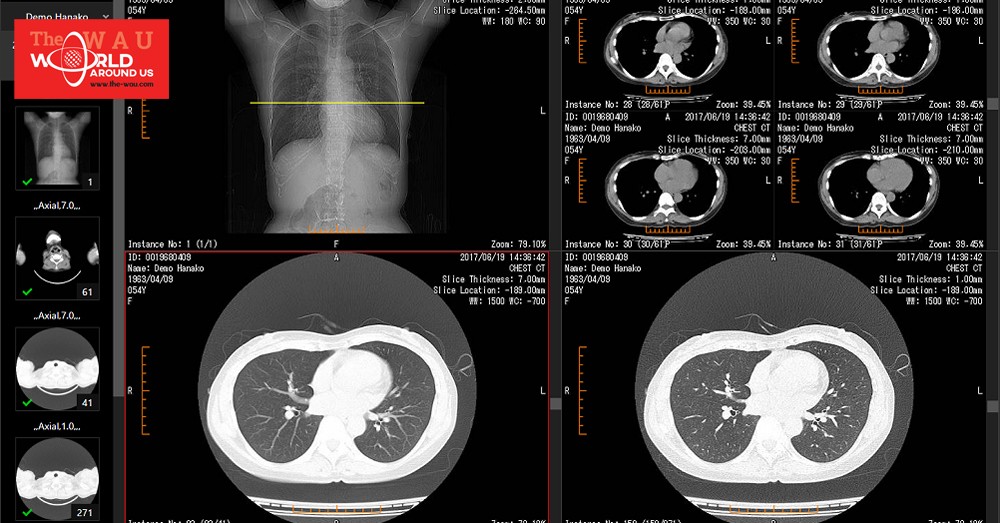

This service enables you to store medical images in the cloud and, simply by accessing a URL from a PC or tablet, to view them from anywhere in the world.

Viewer screen: https://sonicdicom.com/img/release/viewer.png